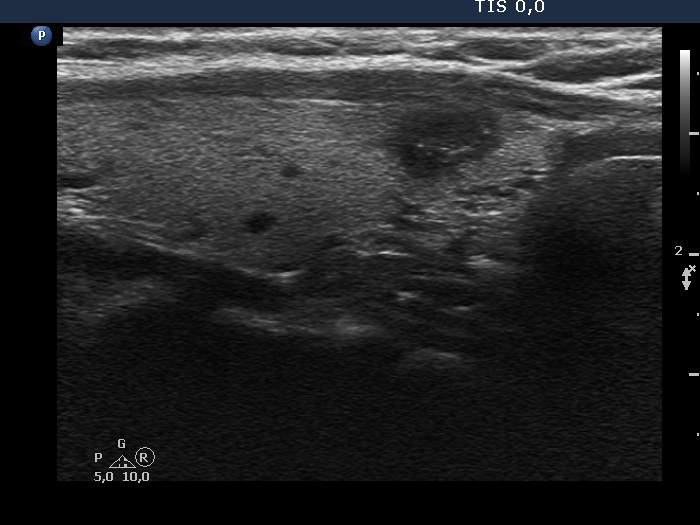

Five months after the first examination (third row of images)

Clinical presentation: The patient had no complaints. She was referred for evaluation of an elevated TSH level.

Palpation: no abnormality.

Laboratory tests: 4.76 mIU/L, aTPO 0,6 U/mL.

Ultrasonography. The thyroid was echonormal. There was a hypoechoic nodule in the ventral part of the left lobe. The ventral borders of the lesion were undefined because the echogenicity of the lesion and the neighboring strap muscle was identical.Suggestion: TSH in a year, ultrasound in two years, in the event of complaints at once.

- Compared with the nodule just after the aspiration with that seen five months later, a spontaneous further decrease can be observed.

- On the second examination, we cannot see cystic portions, therefore the intranodular echogenic figures might cause concern. However, if we take the ultrasound pattern at the previous examination into account, this concern is not justified.

- The presentation of the nodule at the follow-up is an example of non-pathological cause of blur.